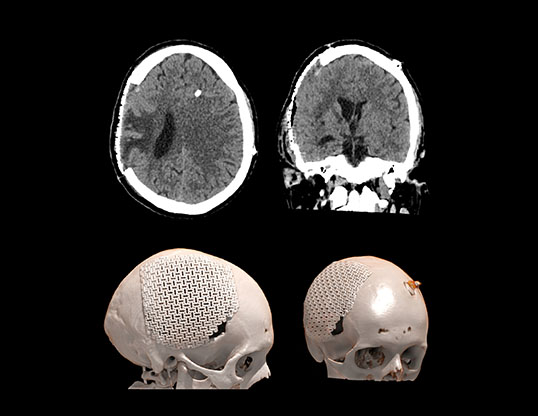

Пациент А., перенесший тяжелую черепно-мозговую травму в ДТП. Состояние после правосторонней гемикраниотомии, эвакуации крупной субдуральной гематомы. Произведена ликворошунтирующая операция с установкой программируемого клапана давления . Через месяц пациент стал предъявлять прогрессирующие неврологические расстройства.

Визуализируется обширная инвагинация кожного лоскута в полость дефекта, смещение срединных структур влево, сдавление САП правого полушария и сглаженность борозд. Причиной данного состояния явилась гиперфункция шунта.

Данному пациенту была произведена краниопластика дефекта черепа, коррекция программируемого клапана давления. Пациент выписан на третьи сутки в удовлетворительном состоянии с полным регрессом неврологической симптоматики.